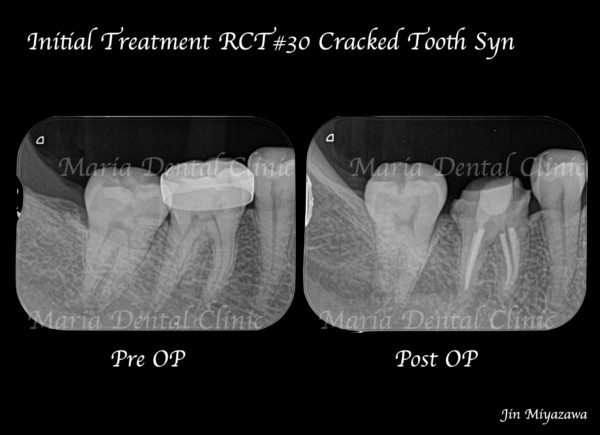

|治療前画像3-1.png)

患者様は、右下の奥歯が痛いことを主訴に来院されました。右側の歯で食べ物を噛むと、鋭く強い痛みがあるとのことです。

右下6番の歯には、金属の詰め物(インレー)が装着されていましたが、レントゲンならびに視診での診査では、虫歯を確認することはできませんでした。また、歯髄の生活反応(※)も正常であることから、一部分補綴(インレー)を除去し、う蝕(虫歯)の確認を行いましたが、金属の下にも虫歯は確認できず、処置後も痛みに変化は見られませんでした。

そこで当院では「クラックシンドローム」を疑い、特別な方法を用いて診査を行いました。

「クラックシンドローム」とは、歯ぎしりや食いしばりなどにより歯に亀裂が入り、咬合時にひび割れが広がることによって、歯髄に知覚過敏のような痛みを誘発するものです。通常の歯髄診査などでは、原因となる歯の特定が困難なため、特殊な器具を使い診査・診断を行うことが求められます。